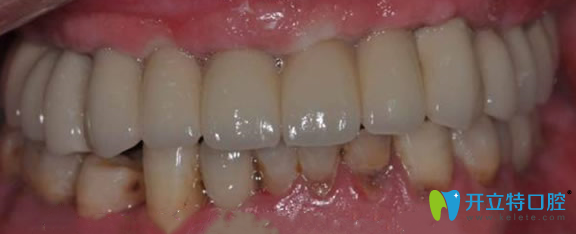

金臺(tái)口腔半口牙缺失術(shù)后效果圖:

南京金臺(tái)口腔門(mén)診讓張叔擁有了整齊的牙齒,見(jiàn)人就夸金臺(tái)口腔田忠奎院長(zhǎng)不光種植牙技術(shù)好,牙齒矯正方面在南京地區(qū)也是赫赫有名。還建議大家一定要到正規(guī)的口腔進(jìn)行口腔診治,說(shuō)的有模有樣的,被樓下的阿姨稱(chēng)為“民間牙醫(yī)”。